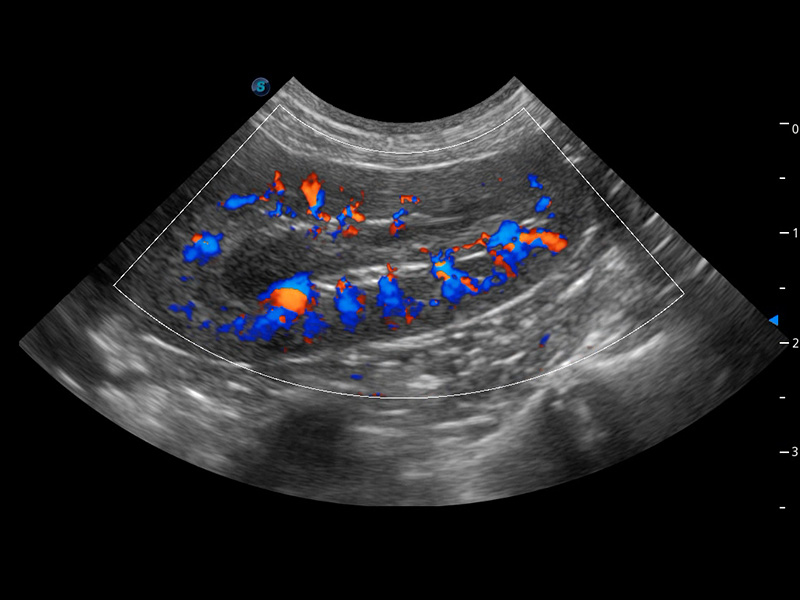

SR Flow 高分辨率血流成像

能够清晰显示细小、低速血流图像,获取传统彩色多普勒技术难以得到的细节和信息。

(犬)肾脏血流